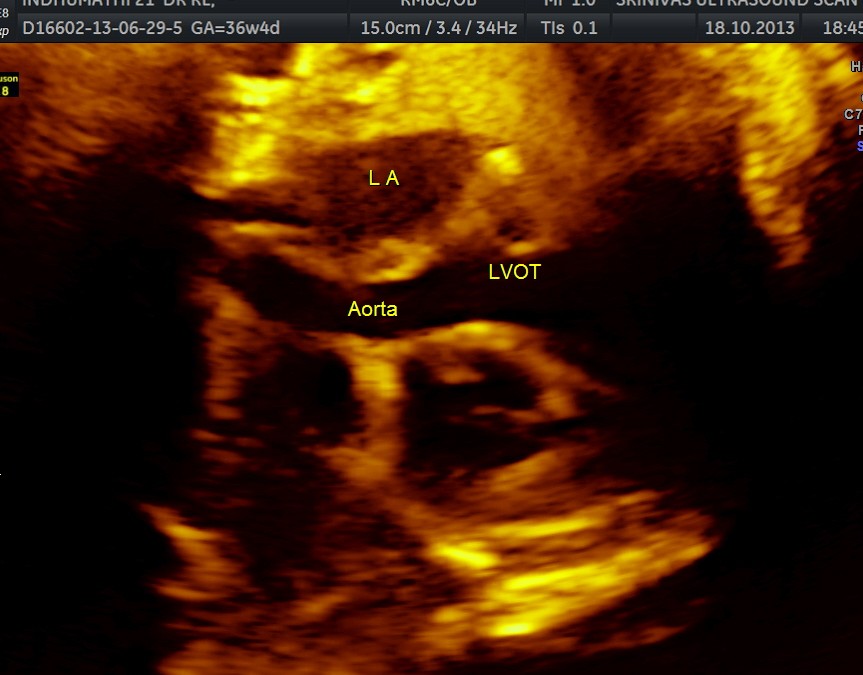

The following are from the 37 weeks scan.

After reviewing the images I could not make out any anomaly as such. The husband again met me and said that a cardiologist after doing an echo showed him a big hole in the heart and wondered how this was missed antenatally. I again requested him to show me the report and subsequently was given the report the next day. The cardiologist has reported an ostium secundum atrial septal defect. I spent some time with the patient explaining the fetal circulation and how it is nearly impossible to report an ostium secundum atrial septal defect antenatally . I also explained to him that immediately after birth a patent foramen ovale also could be mistaken for an ostium secundum atrial septal defect. The patient seemed to have understood and never came after that.